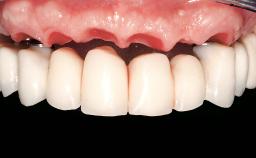

Immediate Loading of Four Implants in the Mandible and Six Implants in the Maxilla and Final Restoration with a Full-Arch Metal Framework FDP and a Full-Arch CAD/CAM Zirconia Framework FDP

A 65-year-old female patient with a failing residual maxillary dentition and a complete mandibular removable denture was referred for consultation and treatment. The patient’s chief complaint was that her upper residual teeth were mobile and she was unable to chew. The patient also asked us to improve the esthetic appearance of her smile. The patient’s desire was a stable and comfortable dentition in both jaws, and she specifically asked for a fixed rehabilitation. The patient reported a history of recurrent caries, endodontic complications, and periodontal disease as main reasons for previous teeth extractions. The anamnesis was negative for bruxism and TMJ disorders. The patient had no systemic diseases, was not on any medication,and did not smoke. The extraoral examination revealed a medium lip line, a wide diastema between the two central incisors (which, according to the patient, had appeared recently), and a partial collapse of the perioral soft tissues, probably due to loss of the correct vertical dimensions.